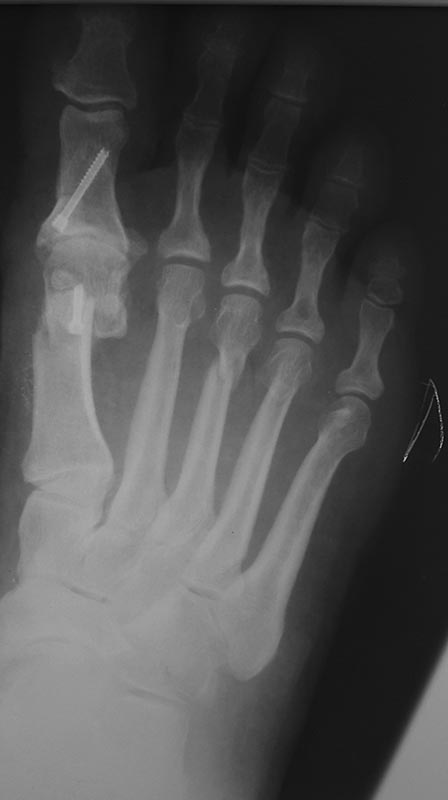

По просьбам трудящихся)) сегодня сделан шеврон Эйкин 3dmmo!)) остеотомия

вышла стабильно!  Накосячил с параболой ,  не дал достаточного

укорочения m1! Нужен опыт!))